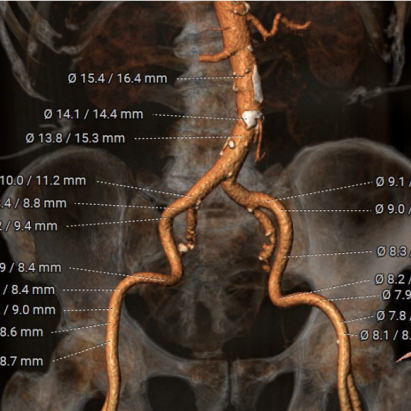

1.89岁高龄,肾功能不全Ⅲ期

2.主动脉瓣环与水平夹角61°,横位心

3.左冠开口低,且患者伴冠脉粥样硬化,冠状动脉左前降支近段中度狭窄,日后可能PCI治疗

4.胸腹主动脉走形呈S形迂曲,管壁散在混合型斑块